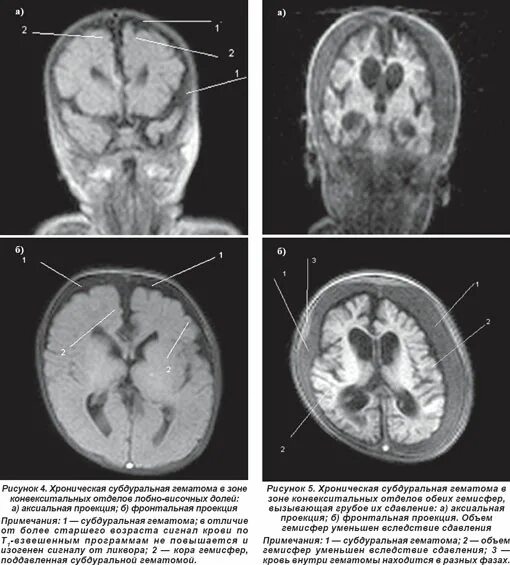

Кровоизлияние в мозг у новорожденного степени